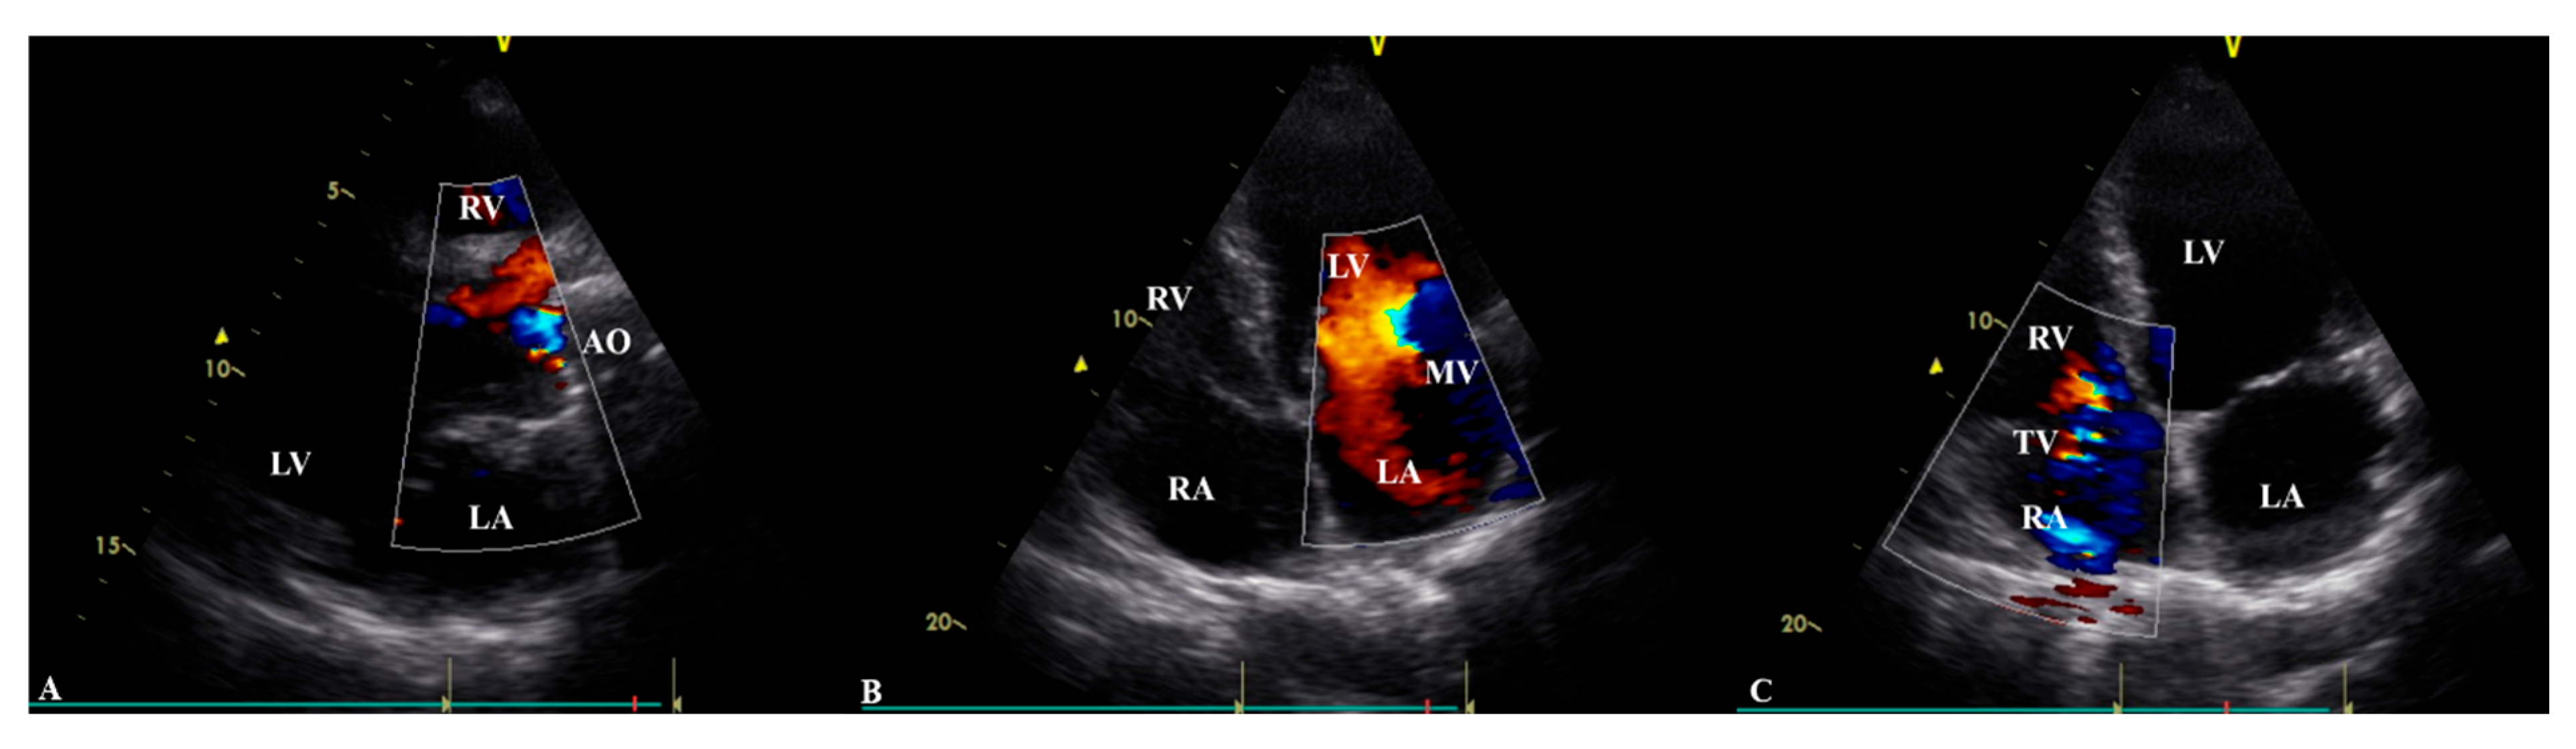

Transthoracic echocardiography (

Table 1) revealed a prosthetic aortic valve and an ascending aortic graft, with mild (Grade I) intraprosthetic regurgitation, eccentric left ventricular hypertrophy, and moderate-to-severe (Grade II–III) mitral valve regurgitation. The left ventricular systolic function was at the lower limit of normal, with an ejection fraction of 50%, while Grade II diastolic dysfunction was identified. The right heart chambers were dilated, with moderate (Grade II) tricuspid regurgitation observed (

Table 1,

Figure 2). A chest CT scan showed scoliosis, postoperative metallic artefacts from prior spinal surgery, and dilatation of the right heart chambers (